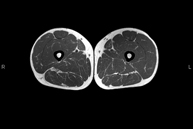

Exploració per estudiar la musculatura i dels tendons que s'originen en aquest nivell, com els tendons isquiotibials, lesió sovint en esportistes. La durada aproximada és de 16 minuts. No empra radiació ionitzant. - RM de Cuixa

Exploració ideal per estudiar les lesions en músculs isquiotibials i quàdriceps, sovint lesionats en esportistes. També permet una bona valoració de tendons i de nervis perifèrics. La durada aproximada és de 20 minuts. No utilitza radiació ionitzan. - RM de Genoll